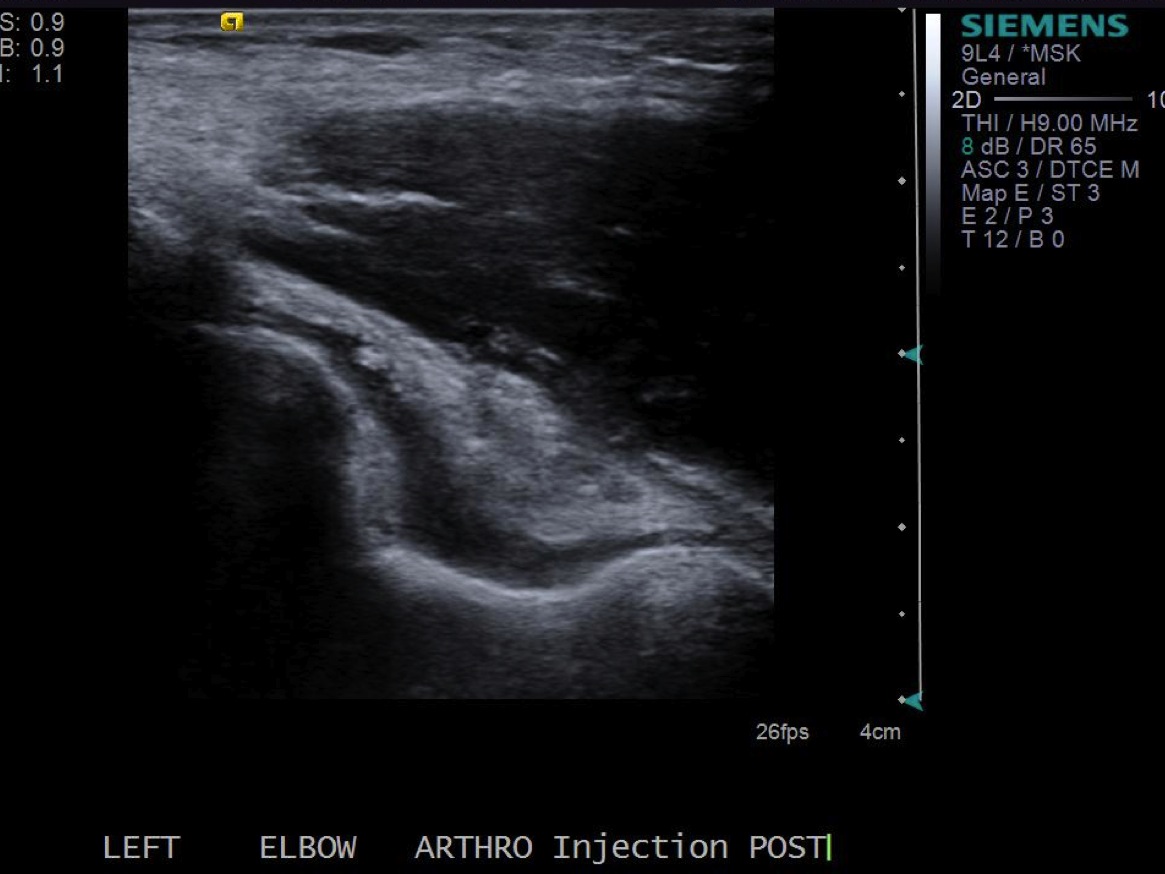

Post procedure images demonstrating distention of the joint in the posterior recess.